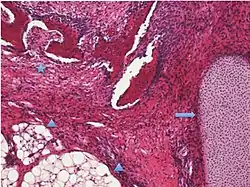

| Germ cell tumor | Mature cystic teratoma | 46.0% | 0.17% to 2%[6] | Cystic, with elements of all 3 germ layers (endoderm, mesoderm and ectoderm).[7] | .jpg) |

| Surface epithelial-stromal tumor | Serous tumor | 25% | 18.5% | Benign serous tumors of the right ovarian cyst are thinwalled unilocular cysts that are lined by ciliated pseudostratified cuboidal or columnar epithelium.[9] |